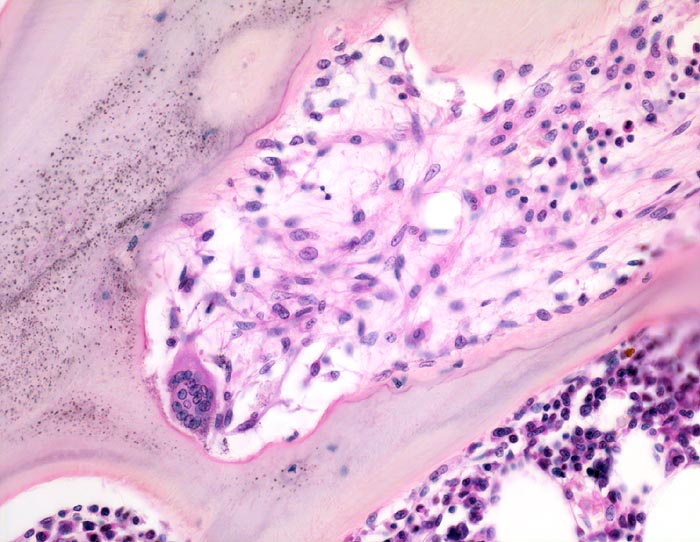

Spongiosabälkchen mit tiefer Resorptionslakune, die das Bälkchen tunnelartig aushöhlt. In dieser Lakune links unten im Bild ein Osteoklast mit >10 Kernen/Schnittebene. Parallel zur Spongiosaoberfläche vermehrt Osteoblasten. Die Resorptionslakune ist aufgefüllt mit lockerem Bindegewebe gebildet von Fibroblasten.

Adenom der Nebenschilddrüse mit primärem Hyperparathyreoidismus. Nephrolithiasis.